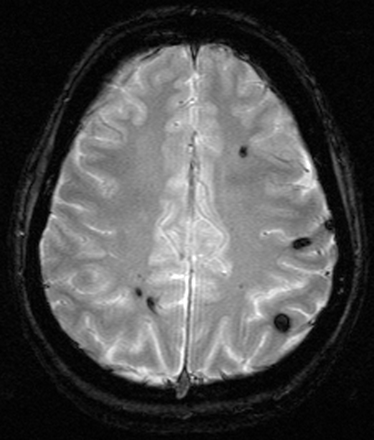

Susceptibility effects increase with higher B0. Although this can cause artifacts, it is also of clear advantage for susceptibility-related imaging such as T2* sequences for detection of hemosiderin (Fig 10) relevant for detection of microbleeding in vascular encephalopathy (36). Cerebral hemorrhage is reliably detected at 3T (37).

Patient with multiple cavernomas inducing large susceptibility artifacts in T2* imaging at 3T, which is indicative of the high sensitivity for susceptibility effects at 3T (TR, 800 ms; TE, 26 ms; flip angle, 20°; bandwidth, 80 Hz/pixel; section thickness, 5 mm; matrix, 320 × 320; FOV, 220 × 220 mm2).